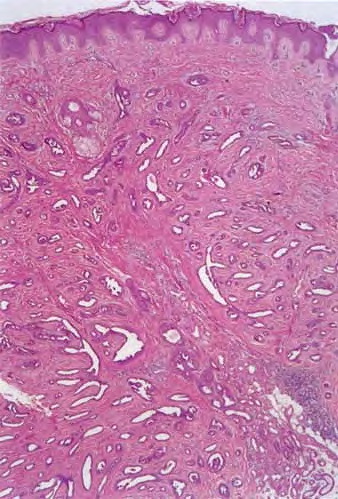

The term tubular adenoma defines a group of benign appendage tumors histopathologically characterized mainly by numerous cystic, dilated, and branching tubular structures in the dermis surrounded by a compressed fibrous stroma. Lesions show either eccrine (tubular eccrine adenoma) or apocrine (tubular apocrine adenoma) differentiation.

This lesion demonstrates a relatively well-circumscribed dermal nodule consisting of numerous cystic, dilated, and branching tubules, surrounded by compressed or focally hyalinized fibrous tissue.